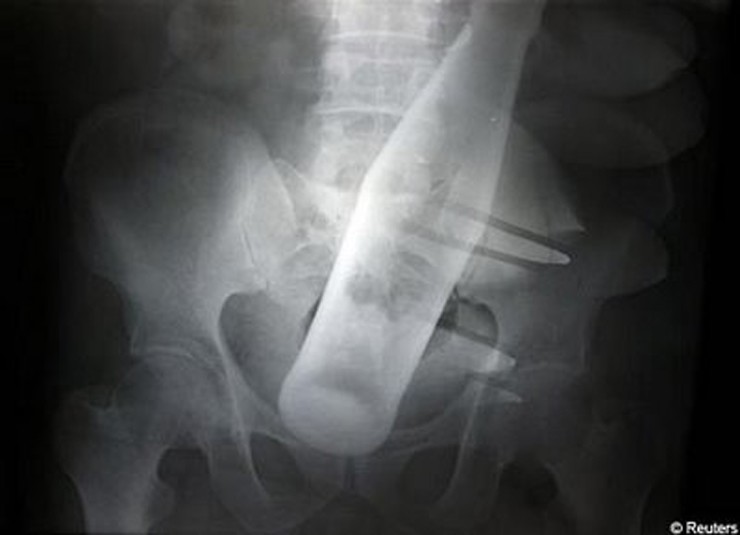

Бутылка

На снимке 60-летний мужчина с бутылкой, которая была вставлена насильно.